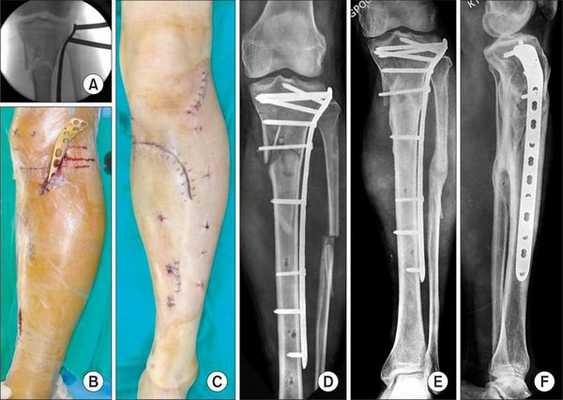

Хирургическое лечение

Хирургическое лечение состоит в открытой репозиции костных фрагментов и остеосинтезе — операции, при которой восстанавливают правильную ось ноги и придают отломкам нужное положение. Процедура проводится под общей анестезией. Подходящую технику остеосинтеза врач подбирает в зависимости от участка перелома.

![Остеосинтез]()

При использовании металлоконструкций кости голени сращиваются в среднем через 3-3,5 месяца после операции. Удалять конструкции по медицинским показаниям можно не ранее, чем через полгода. К таким показаниям относятся риск перфорации кожи и травмы мягких тканей. Также конструкцию нужно убрать, если она мешает разработке сустава, сдвинулась или поломалась.

Если конструкция мешает пациенту, её можно удалить, но не раньше, чем через год.

Аппараты внешней фиксации, например стержневые фиксаторы или аппарат Илизарова, применяют только временно, пока состояние пациента нестабильно и нельзя провести операцию.

Лечебная тактика определяется состоянием пациента и особенностями перелома. При изолированных травмах активно используются компрессионно-дистракционные аппараты, при сочетанных повреждениях на раннем этапе, как правило, накладывается скелетное вытяжение, а в последующем, после заживления раны, выполняется остеосинтез костей голени пластиной, винтами или блокирующими стержнями, либо осуществляется внеочаговый остеосинтез аппаратом Илизарова.